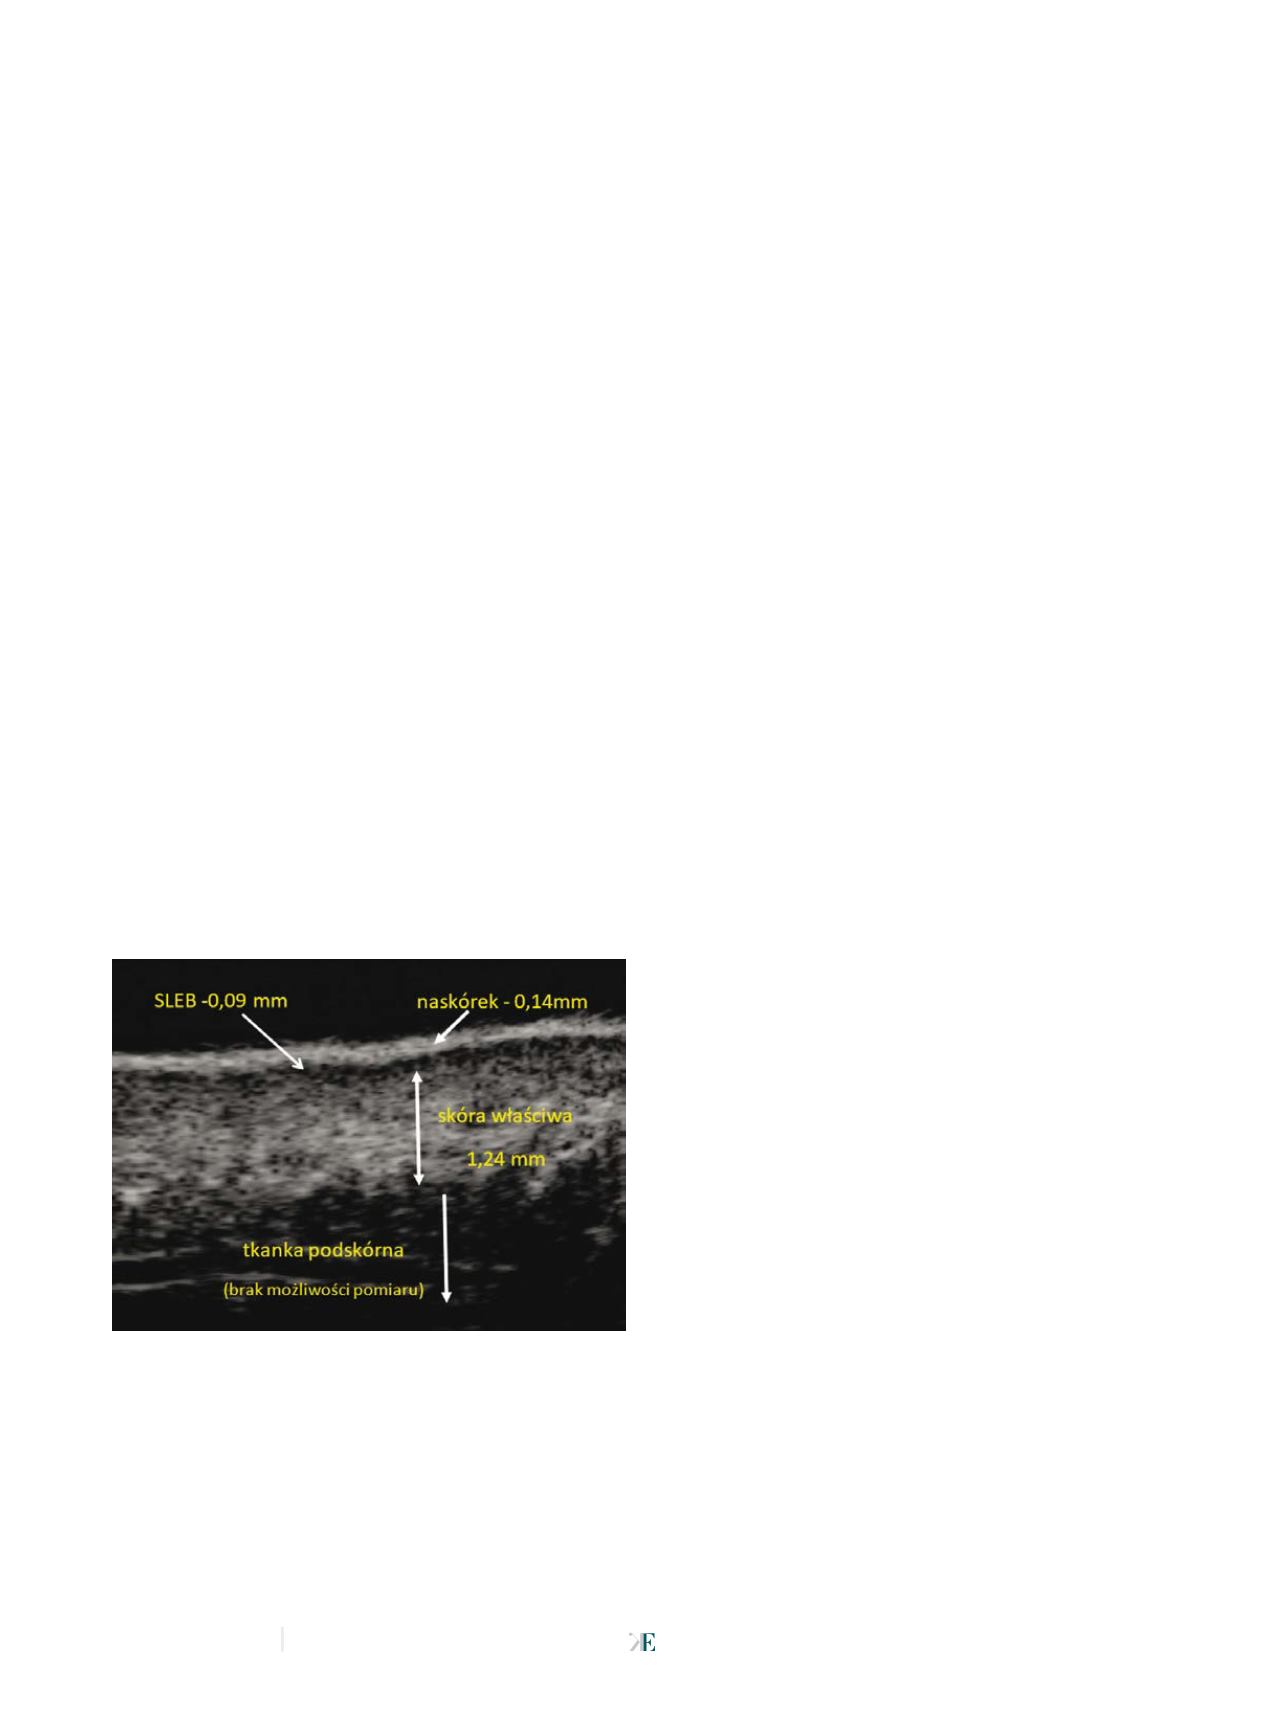

W ultrasonografii zaawansowanie starzenia skóry odzwier-

ciedla ocena hipoechogenicznej linii, znajdującej się tuż pod

hiperechogenicznych naskórkiem (fot. 1). Linia ta zwana jest

warstwą SLEB (

subepidermal low-echogenic band

) [7]. Powiąza-

nie SLEB z fotostarzeniem się skóry znajduje potwierdzenie

w literaturze [8-12]. Autorzy wykazują korelację między skalą

szarości SLEB w odniesieniu do fotostarzenia. Wraz z wiekiem

i ekspozycją skóry na promienie ultrafioletowe UV (

ultraviolet

radiation

), SLEB wykazuje spadek echogeniczności [13]. Z uży-

ciem aparatów z głowicami wysokiej częstotliwości możliwy jest

pomiar liczby pikseli poszczególnych fragmentów skóry. Na tej

podstawie, wykonując zabieg mezoterapii, można ocenić sku-

teczność zabiegów oraz porównać skuteczność poszczególnych

preparatów kosmetycznych bądź leków, używanych w terapii.

Udowodniono, że przy właściwym doborze metody mezoterapii,

echogeniczność warstwy SLEB rośnie. Informacje te dają moż-

liwość zindywidualizowania zabiegów intradermoterapii, co

przełoży się na ogólny wzrost skuteczności tego rodzaju terapii.

Fot.1 U

ltrasonograficzny obraz wysokich częstotliwości skóry twarzy z widocznym pasmem

o obniżonej echogeniczności – SLEB.

Źródło:

Archiwum własne autorów, aparat Derma med, Dramiński